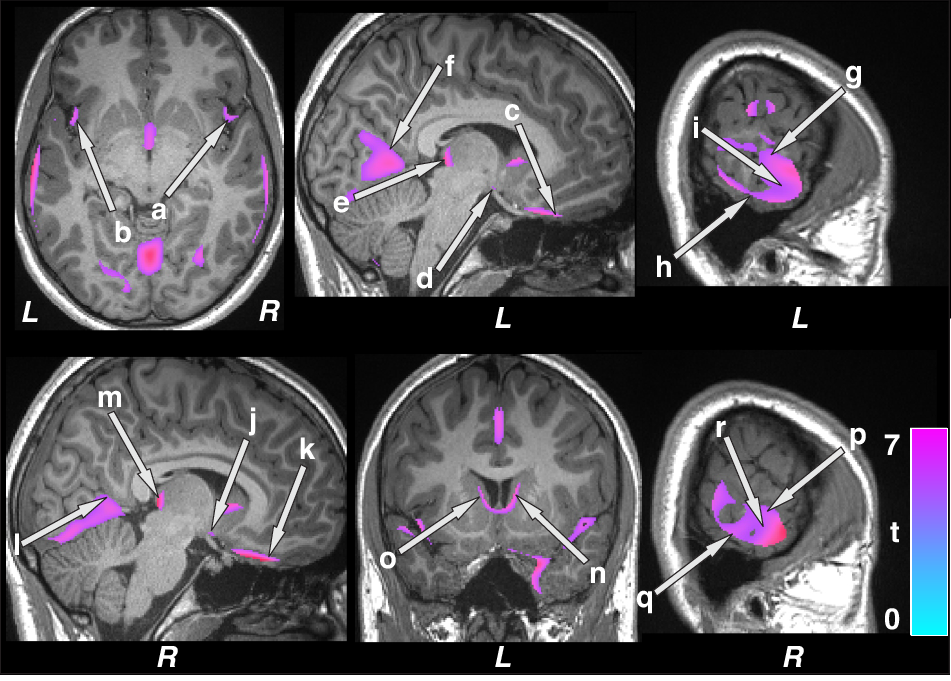

Fig. 2: Brain sites with lower regional gray matter volume in patients with epilepsy compared to control subjects.

Brain regions with reduced gray matter volumes were observed in the bilateral insula (a, b), ventral medial prefrontal cortices (c, k), hypothalamus (d, j), posterior thalamus (e, m), lingual gyrus (f, l), inferior (h, q), mid (i, r), and superior (g, p) temporal cortices, and caudate (n, o) in patients with epilepsy over controls. Figure conventions are the same as in Fig. 1.